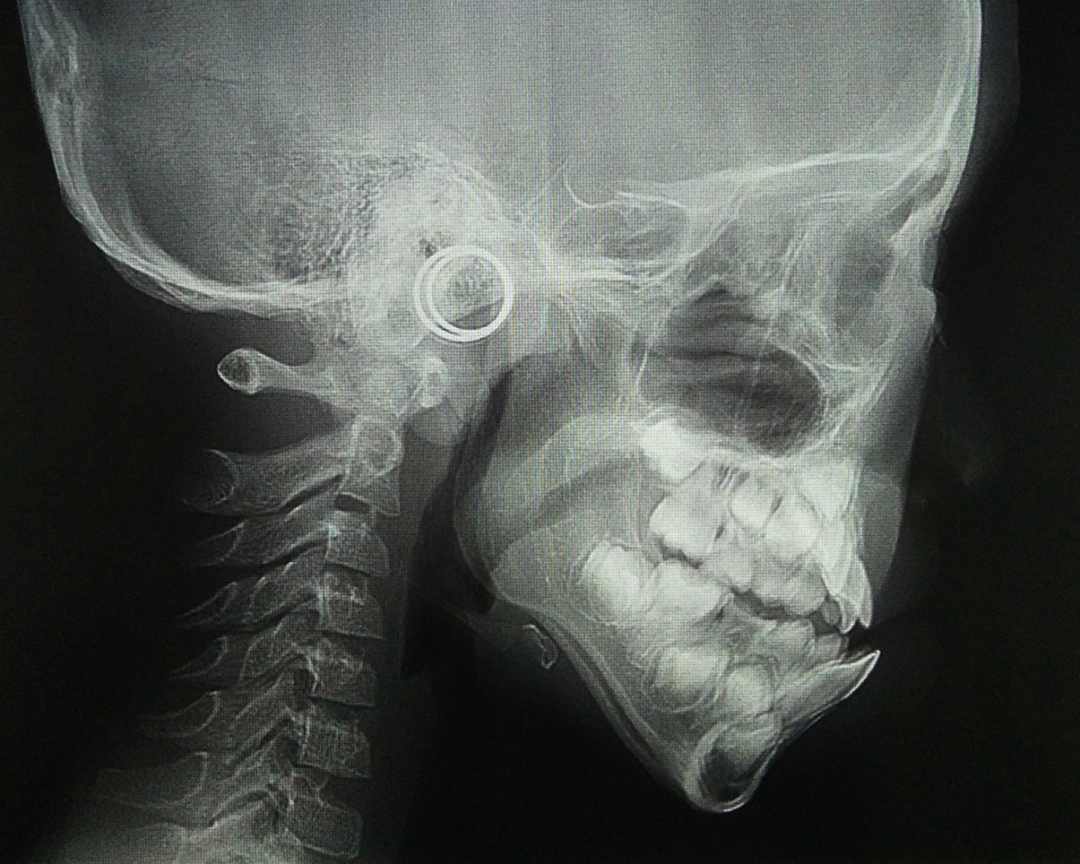

2、面型不好看,尤其是嘴凸没有下巴,我觉得这一点会涉及到健康,当这个孩子是小下颌畸形的时候,它会带来整个呼吸道狭窄。

如果我们拍一张片子的话,有些孩子呼吸道就很窄,下颌骨有跟舌骨是连着的,舌骨再往下是跟气道连着的,所以小下巴的孩子有的时候睡觉就会打呼噜,呼吸不通畅。

如果你呼吸不通畅,也会影响全身发育,可能个子长不高,智力也会受到一定的影响。